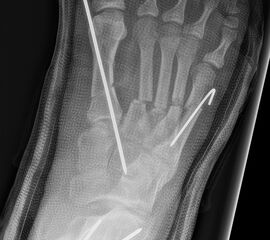

Abb. 2 a-c: offene Wachstumsfugen MT I Basis und Zehen (a), teilweise geöffnete Wachstumsfugen (b) und geschlossene Wachstumsfugen (c).

Zum Lesen der Bildbeschreibung und zur Vollansicht bitte die Bilder anklicken. Bilder: A. Helmers.